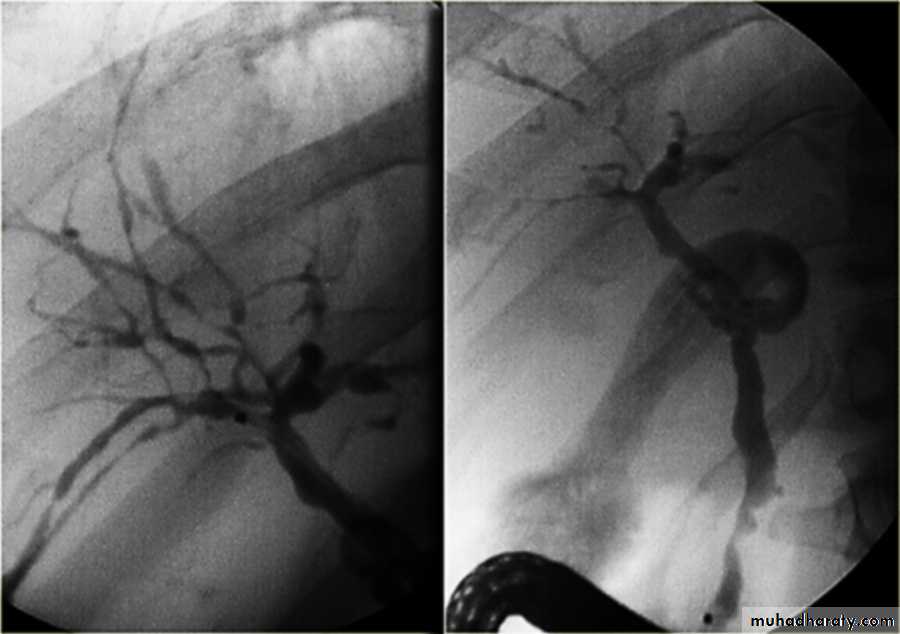

Cholangiogram: typical “beading” or “pruning” of extra- and/or intra-hepatic bile ducts (strictures).

MRCP (of choice)

ERCP (only if intervention is planned)